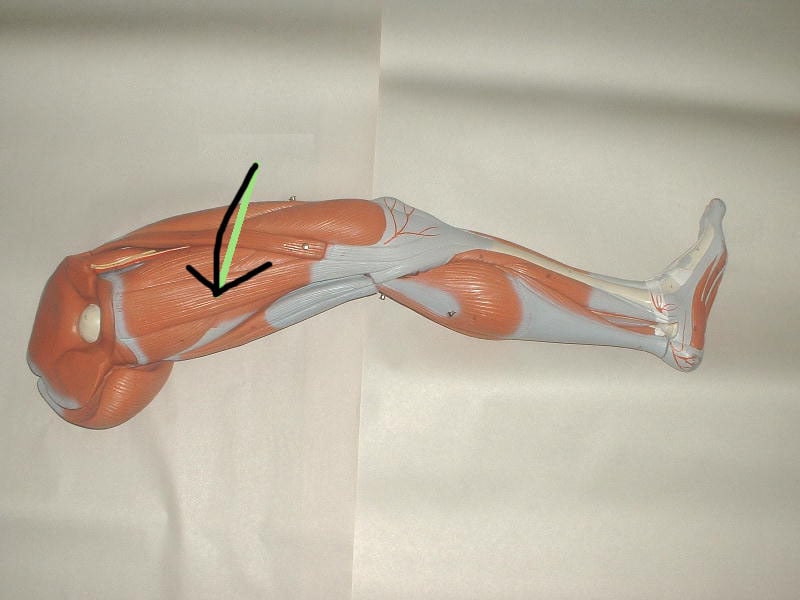

Анатомия и Функции Мышцы Adductor Magnus